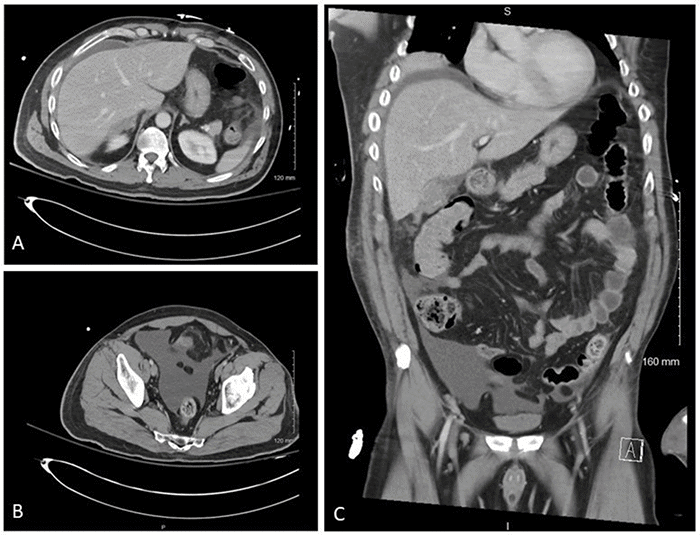

On hospital day 3, the patient’s confusion, attributed to his traumatic brain injury, persisted, but he was able to verbalize worsening abdominal pain. Physical examination revealed tenderness to palpation in the right upper quadrant. No fever or leukocytosis was present. The patient’s total bilirubin level had slightly increased from 0.6 mg/dL to 1.3 mg/dL. Repeat CT of the abdomen and pelvis demonstrated a new perihepatic fluid collection extending down the right paracolic gutter into the pelvis (Figure 1). Due to concerns for potential bowel injury, the patient was taken to the operating room for exploratory laparotomy.

Figure 1. Radiographic Evidence of Intra-abdominal Fluid Accumulation following Delayed Gallbladder Rupture. Published with Permission.

CT of the abdomen and pelvis on hospital day 3 demonstrating intra-abdominal fluid accumulation. (A) Axial view showing free fluid in the right perihepatic space. (B) Axial view showing ascites in the lower pelvis. (C) Coronal view showing free fluid in the right perihepatic space, right paracolic gutter, and lower pelvis